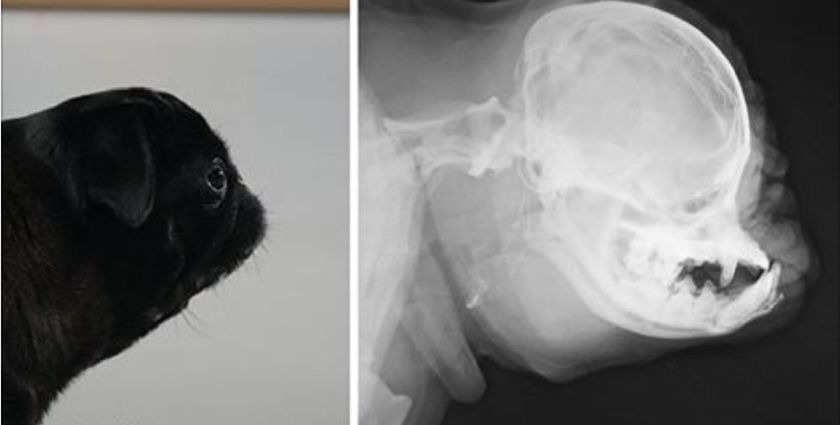

La brachycéphalie est une condition anatomique chez le chien qui présente une partie faciale du crâne nettement plus courte et plus large, un nez plat, une langue et une cloison nasale hypertrophiées, une ouverture nasale étroite, souvent des dents manquantes et une poitrine large.

- Radiographie et échographie thoraciques. Ces examens permettent d'évaluer la taille du système respiratoire : l'état et le degré de rétrécissement des voies aériennes, la taille des narines, la radiodensité des champs pulmonaires et la forme du cœur, ainsi que d'autres anomalies associées au syndrome brachycéphale. Ils contribuent à identifier d'éventuels problèmes de santé liés aux particularités anatomiques et les pathologies associées au syndrome brachycéphale (insuffisance cardiaque, pneumonie, etc.).

Un examen visuel du chien suffit généralement au vétérinaire pour établir un premier diagnostic. Compte tenu de sa structure crânienne brachycéphale caractéristique, la cause des problèmes respiratoires est généralement évidente. Tous les examens complémentaires visent à déterminer la gravité de la pathologie et à identifier d'éventuelles complications.

- La tomodensitométrie (TDM) et l'imagerie par résonance magnétique (IRM) permettent d'évaluer l'état des tissus mous et osseux des voies respiratoires.